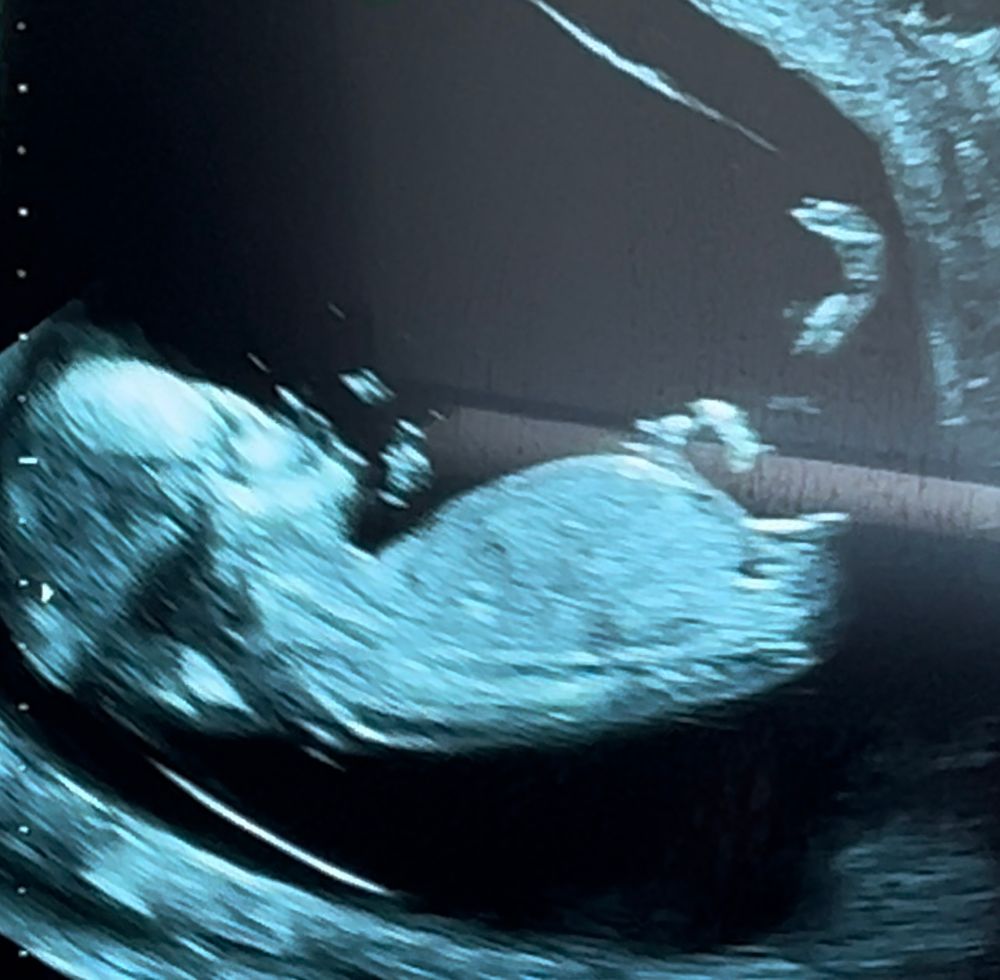

Пол ребенка на 13 неделе

Я не узист, но я тоже вижу, что это 100% девочка.

До 16 недели половые органы внешние только формируются. Поэтому до могут(!) выглядеть одинаково. Конечно,ошибка может ещё быть. Это пока что не научный метод,по половому бугорку гадать.

Тут явно девочка, у меня на первом скрининге точно так же было

Девчуля)

В данном ракурсе девочка)) ☺️🌸